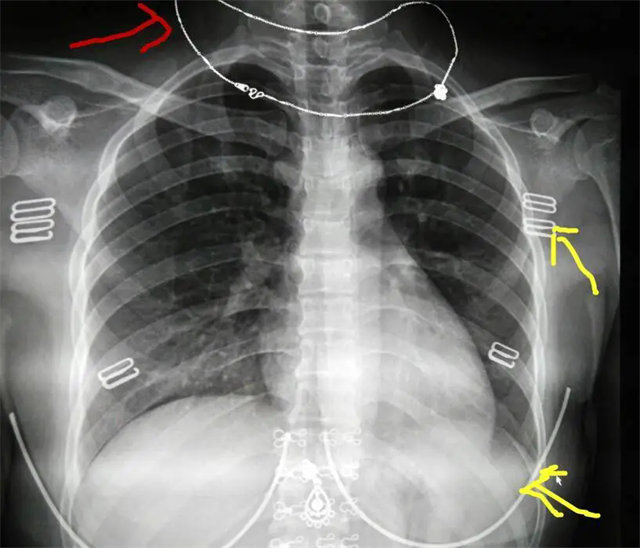

缺陷:左肩胛骨部分與左肺野重疊。

解決:使患者左肩旋前緊貼成像件重新曝光。